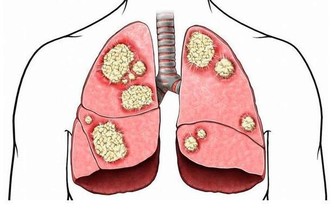

這是因為氧化應激與細胞癌變息息相關,

人體缺硒時無法阻攔氧化應激對細胞帶來的損傷,進而會增加罹患癌症的風險。

德國一個研究所對此展開了研究,結果發現缺硒會使肝癌的發病率提高10 倍。

與血硒水平較高的人相比,缺硒的個體罹患肝癌的風險要高出5 到10 倍。